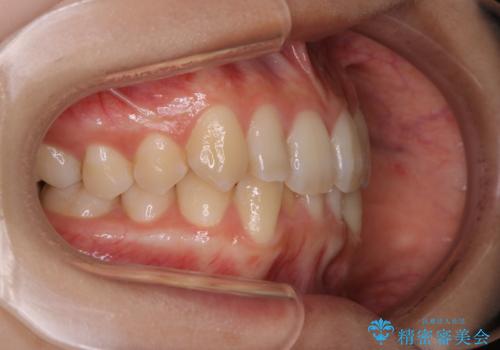

- 上の前歯が1本後ろに入ってしまっていることが気になるとご相談にいらした方です。

元々下の前歯が1本欠損しており、上下の噛み合わせや、歯のサイズバランスを考慮しながら治療を行いました。

クロスバイトしている歯が深く噛み込んでおり、この歯を外に出してくる際に強い咬合力が加わると歯が失活する恐れがあることを説明し、合わせて咬筋へのボトックス注入を行いました。

下顎切歯が1本欠損しているため、上顎前歯部を少しずつストリッピングして、上下の噛み合わせ、バランスの向上を図りました。